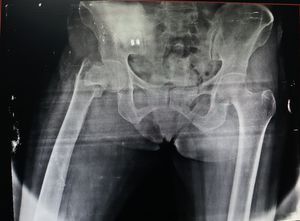

Right Thigh

Injury

Neck

Femur

Injury neck of femur..Near greater trochanter